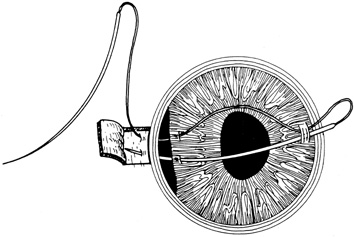

With surgical repair of corneoscleral lacerations, the primary goal is to achieve a watertight globe and maintain structural integrity. Secondary goals include removing any disrupted lens fragments and vitreous, repositioning any uveal tissue, relieving vitreous incarceration, removing any intraocular foreign bodies, and restoring normal anatomic relationships. A methodic surgical strategy is essential for injury repair. Such a stepwise schema affords the surgeon a standard and reproducible approach to the protean manifestations of penetrating anterior segment trauma (Fig. 1).